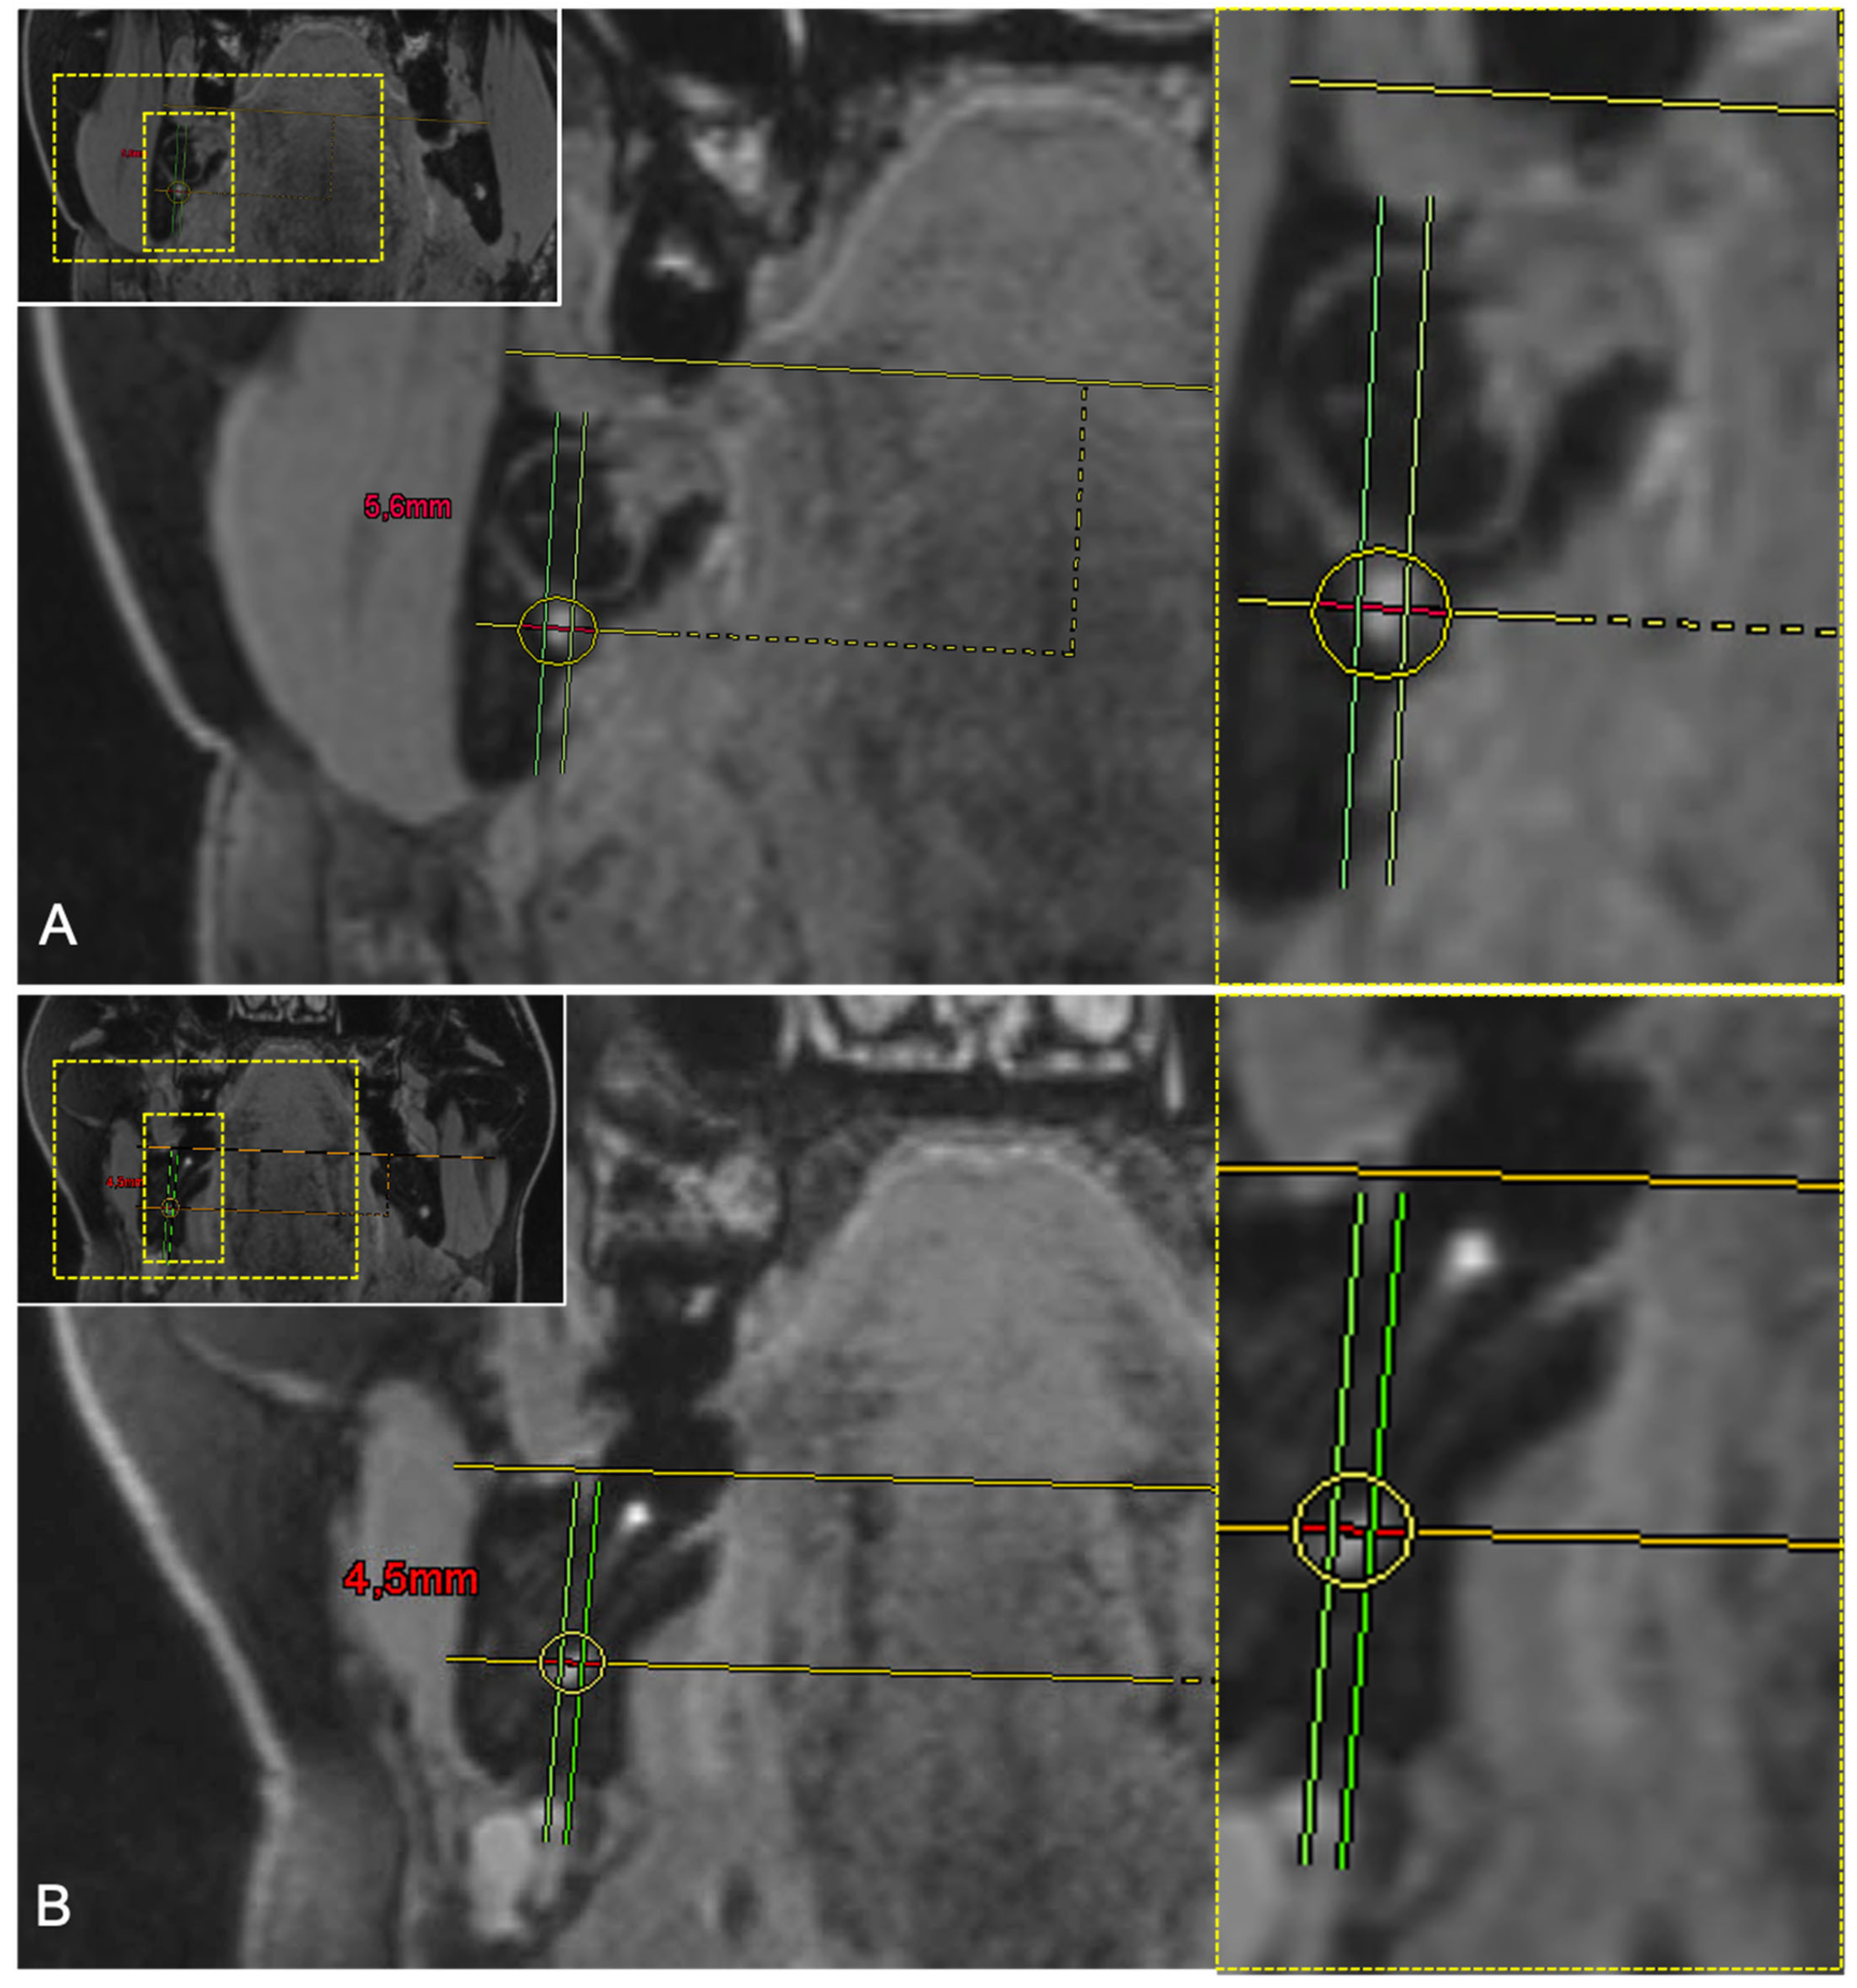

| Third Molar | Axial | Sagittal | Coronal |

|---|---|---|---|

| IAC in CBCT | 3.9 ± 0.85 mm | 4.04 ± 1.23 mm | 5.3 ± 1.03 mm |

| IAC in MRI | 4.18 ± 0.97 mm | 3.76 ± 1.1 mm | 5.49 ± 0.83 mm |

| IAN in MRI | 2.63 ± 1.19 mm | 2.38 ± 0.89 mm | 4.12 ± 0.98 mm |

| Conversion factor IAC (CBCT): IAN (MRI) | 2.04 ± 1.953 | 1.86 ± 0.96 | 1.258 ± 0.394 |

| Conversion factor IAC (MRI): IAN (MRI) | 2.367 ± 2.413 | 1.755 ± 0.742 | 1.374 ± 0.252 |